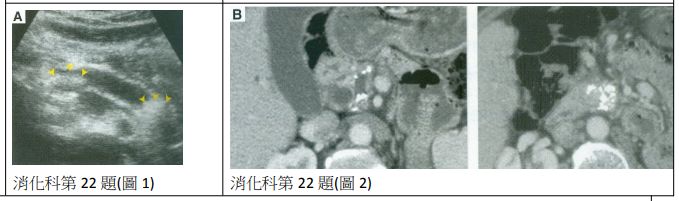

22. 37歲男性患者,主訴慢性腹痛一年以上,有止痛藥使用習慣,且最近有腹瀉、體重減輕現象,腹部超音波(圖1)及電腦斷層檢查結果(圖2),此患者可能出現下列的併發症(complication),除了 (A)黃疸 (B)胃腸出血 (C)維生素B1吸收不良 (D)葡萄糖耐受異常(impaired glucose tolerance) (E)皮下脂肪壞死(subcutaneous fat necrosis)